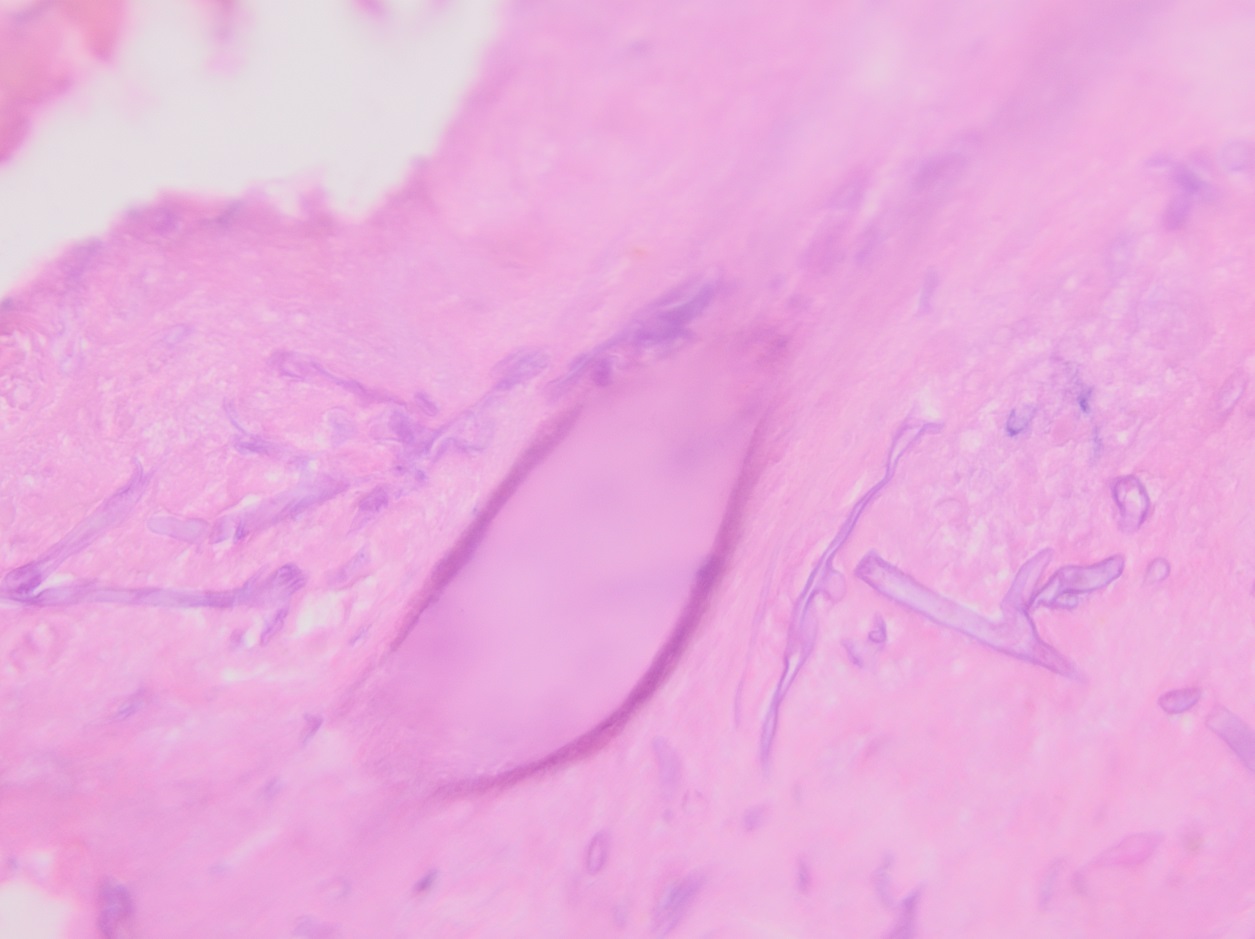

Culturing Histoplasma from clinical specimens is definitive, but it can take 4-8 weeks due to the slow growth of the fungus. The colonies appear white at young growth, have a cottony, cobweblike-aerial mycelium and can mature into brown or grey color on reverse (Figure 1, top) 8. Microscopic examination of mold colony using lactophenol cotton blue preparations reveals the characteristic large, rounded, tuberculate macroconidia (circular structures with roughened/spiked edges) originating from short, hyaline conidiophores (Figure 1, bottom). Histoplasma capsulatum appears as small (2-5 μm), oval, intracellular yeast cells typically found within macrophages. The yeast may exhibit a clear space which may appear like a capsule, but is actually a retraction artifact due to the processing of the specimen. Staining with GMS or periodic acid-Schiff (PAS) highlights the yeasts9. Molecular methods such as PCR and sequencing have been shown to detect cases of Histoplasma as well.